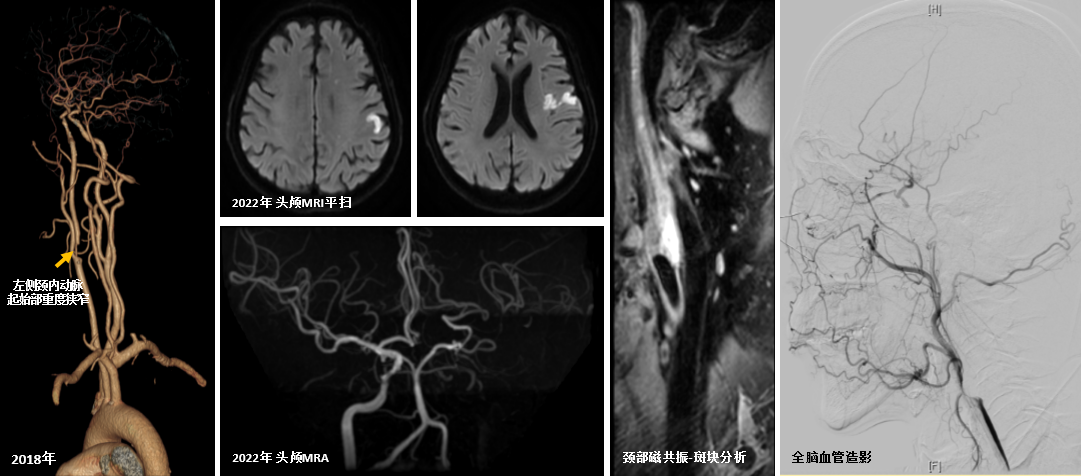

那年,因一次骑行事故,患者被转运到我院并诊断为蛛网膜下腔出血,排查颅内出血原因的过程中意外发现左侧颈内动脉起始部重度狭窄。在颅内出血病情平稳后,患者开始口服脑血管病一级预防药物。然而,规律的药物治疗并没有扼住血管病变加重的步伐,按时体检发现颈部斑块竟逐年增大,终于在2个月前,患者脑梗了!当我们探寻脑梗原因时,很遗憾地发现患者左侧颈内动脉从起始部开始全程闭塞,管腔内出血性斑块印证了患者本次脑栓塞正是由于颈内动脉起始处不稳定的大斑块突然崩解碎裂所致(图1)。

图1:2018年头颈CTA示左侧颈内动脉起始部重度狭窄。2022年3月头颅MRI-DWI序列示左侧颈内动脉供血区多发脑栓塞病灶,头颅MRA可见左侧颈内动脉全程闭塞,颈部斑块分析提示左侧颈内动脉起始部斑块内出血,全脑血管造影可见左侧颈内动脉闭塞,颅内段血流由颈外动脉向颅内代偿。

在保守药物治疗的基础上,我们第一时间组织了科内讨论,脑血管介入组一致认为患者有必要做全脑血管造影检查。造影结果同预想一致,患者左侧颈动脉管腔闭塞(图1)。但是好在,患者多年的颈动脉狭窄迫使颅内生成了良好的侧枝循环代偿,以保证颈内动脉的重要分支血供充足。然而侧枝毕竟不比主干,开通主干道,或许才是真正改善颅内血流、预防远期卒中的最佳选择。